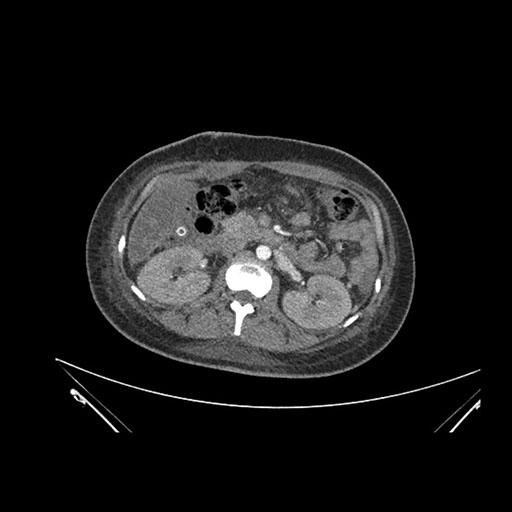

Imaging Analysis

Look through the patient's CT scan to identify any areas of concern for the necessary procedure.

Axial Arterial

Based on initial findings, which issue(s) would you be most concerned about?